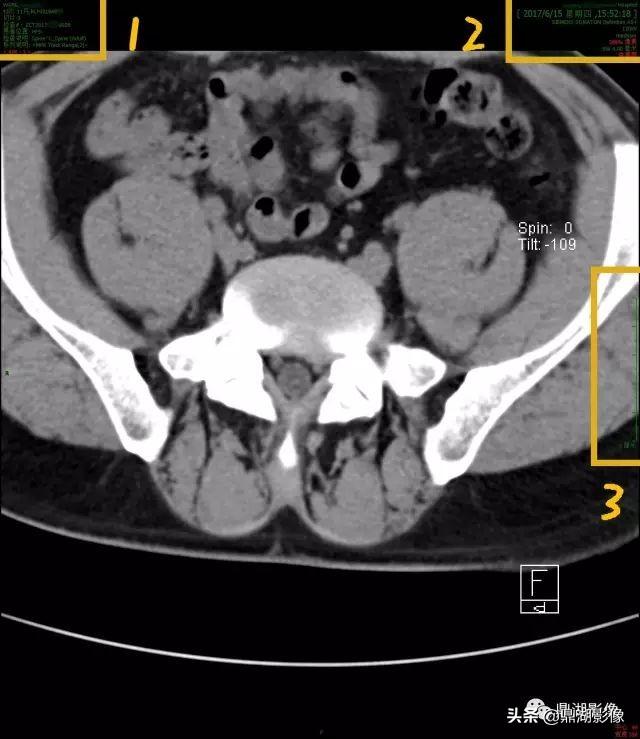

CT

这是一张影像片子中的一个层面/一张图像,图像一般分为几个区,右上为患者及检查信息,左上为机器及图片信息,左下为扫描条件,右下为显示视野。

图中框内标记的A、P、R、L为方位,分别为前后右左;黄色标记3区指向为刻度尺比例,1分隔为1CM,可自行对比量病变大小。

放大1区

1.患者姓名,一般为汉语拼音,有的是汉字标示;

2.患者年龄、性别及影像检查号,其中M为男性,F为女性;

3.影像登记流水号,告诉患者登记的顺序,如图中说明这个患者是2017年6月15号第29个登记的;

4.图像编号,图中这是第3副图;

5.检查部位为L_Spine为腰椎

放大2区:

1.所做检查医院名称,一般带有XX Hosptial或XX医院;

2.检查日期,顺序为年月日;

3.检查时间,精确到秒;

4.所做机器型号,图中为SIEMENS SOMATOM Definition CT机;

5.120KV 是扫描管电压

6.meduser是西门子的meduser账户,可以忽略

7.SW为层厚,图中检查层厚为4.00mm